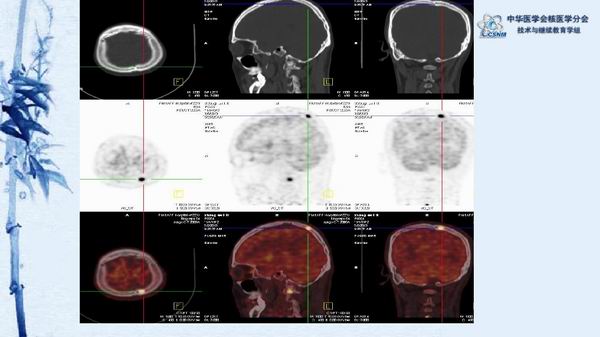

病例49:PET-CT显像诊断淋巴瘤相关噬血细胞综合征一例-【CSNM继教学组】程兵 郑州大学第一附属医院